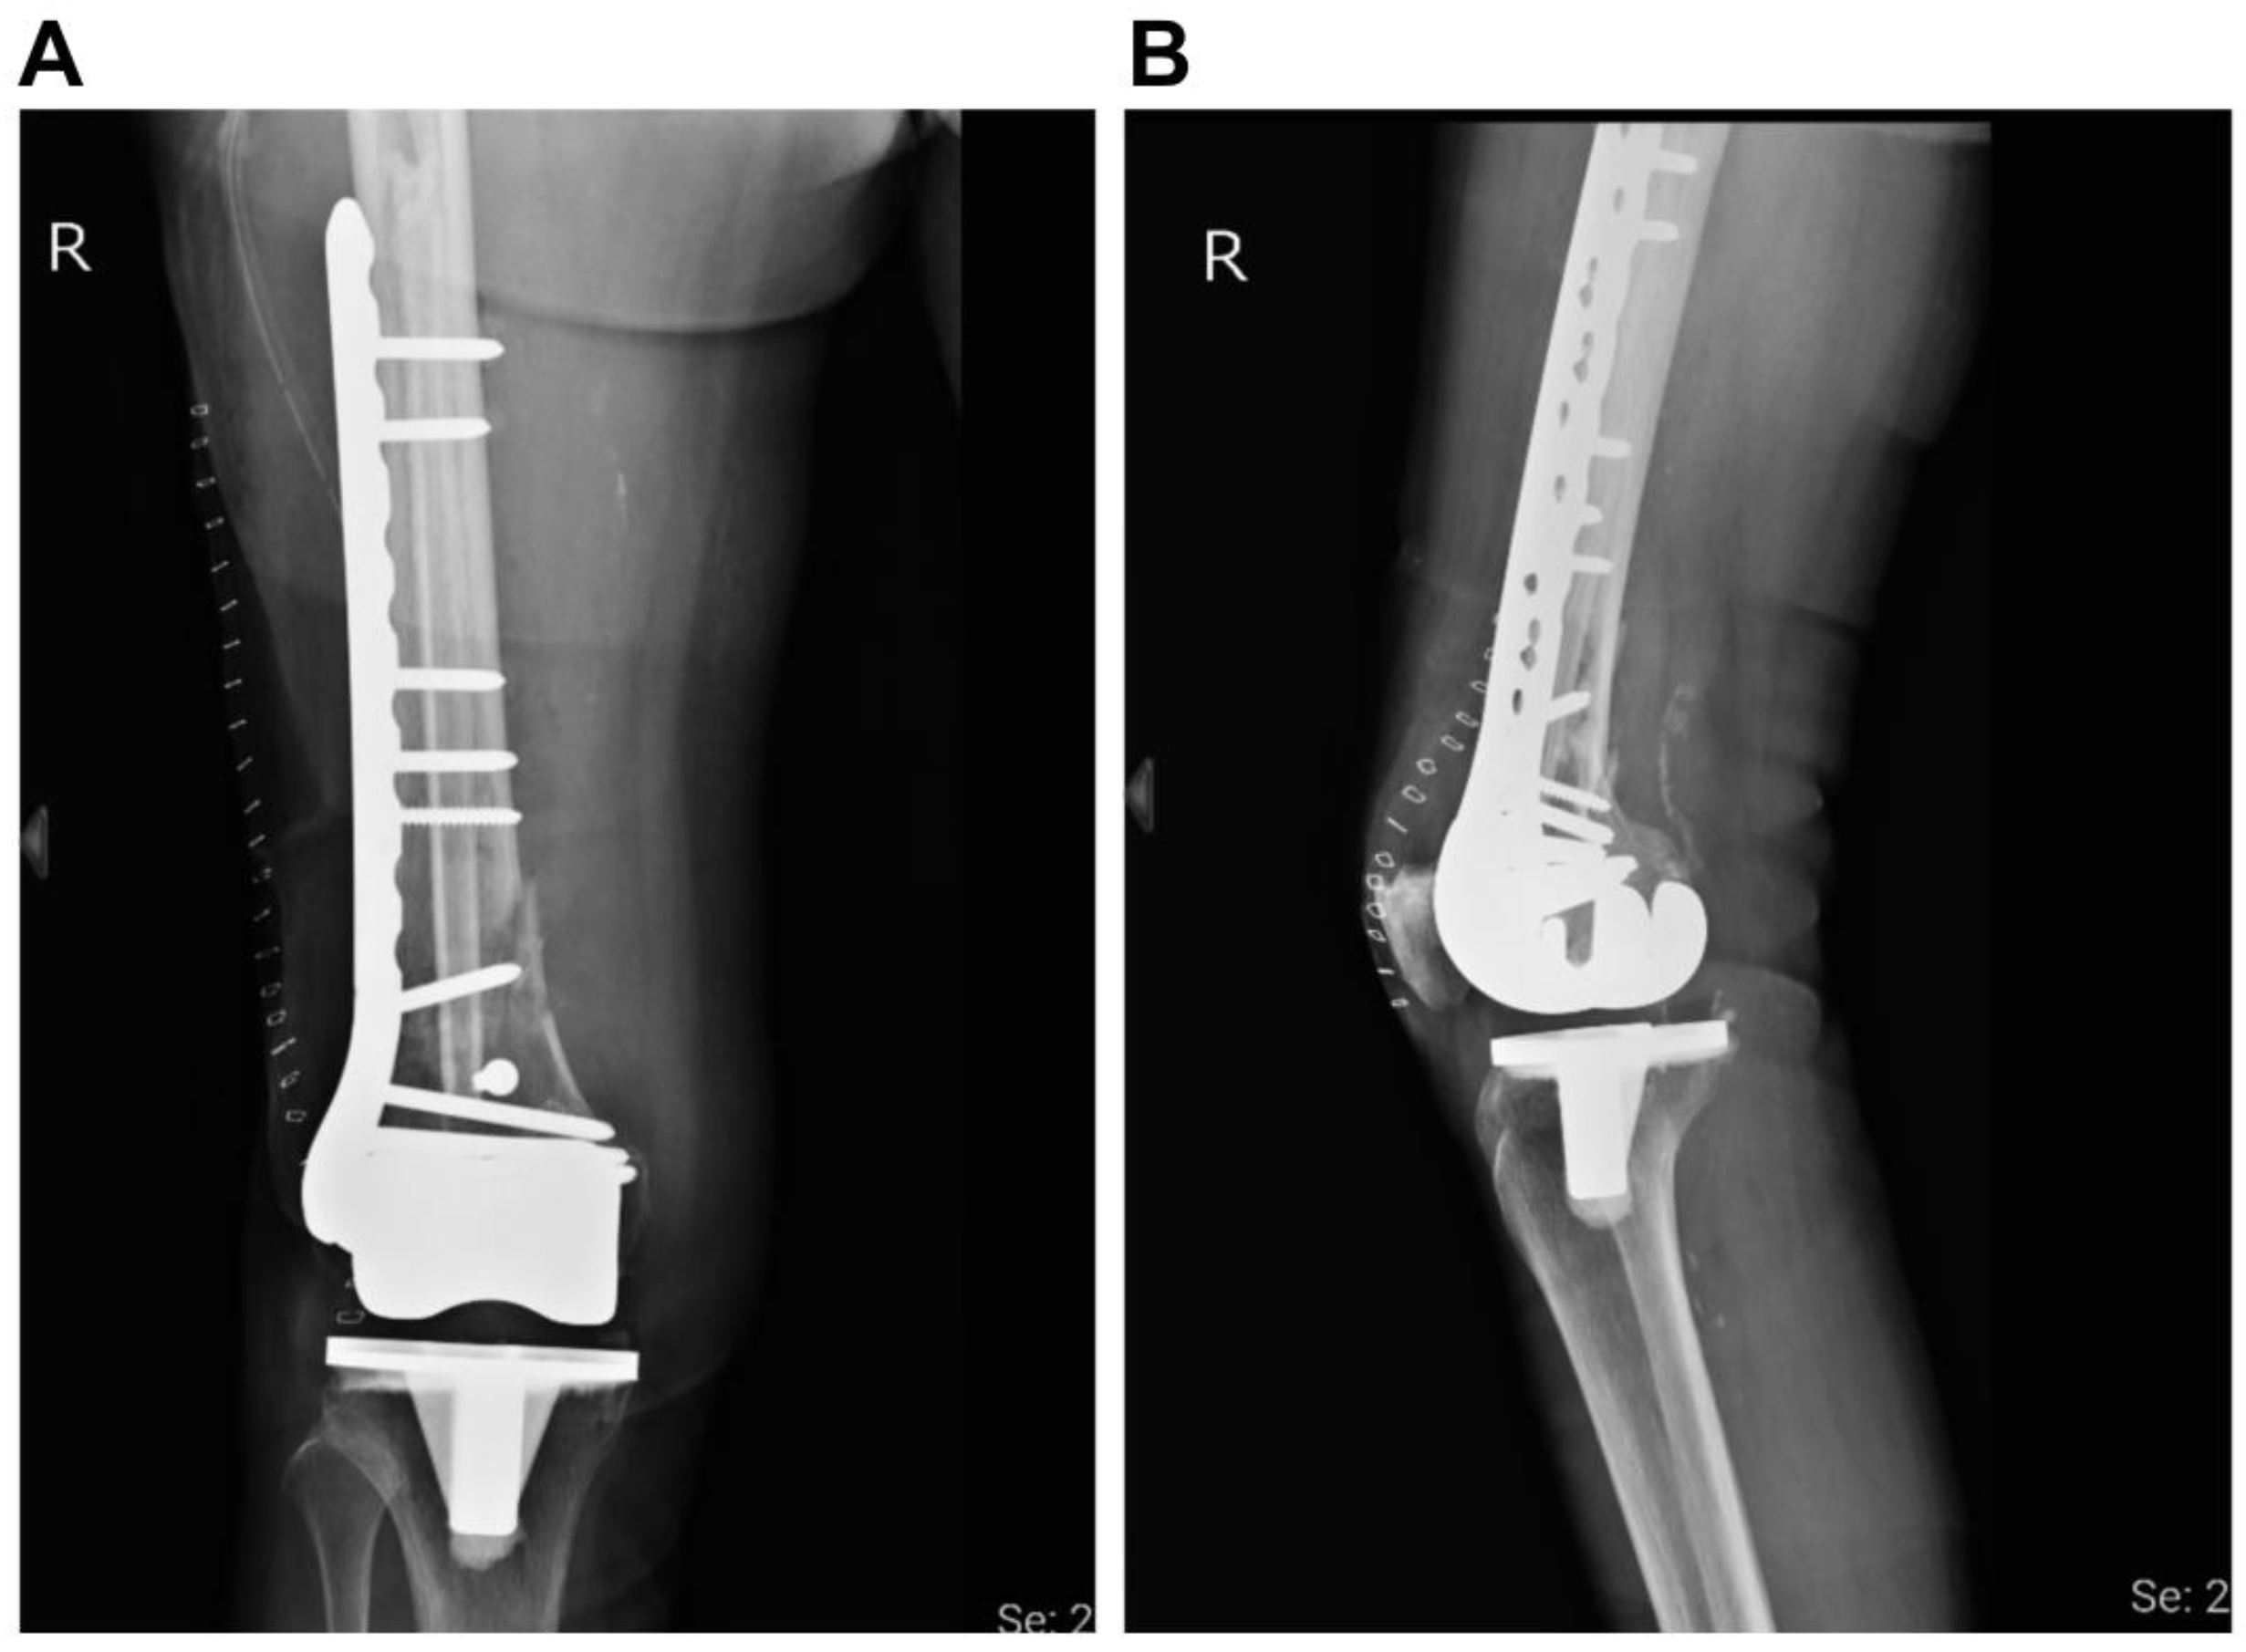

Successful Plate Fixation with Long Intramedullary Fibula Bone Graft for Periprosthetic Femur Fracture: A Case Report

2. Case Report